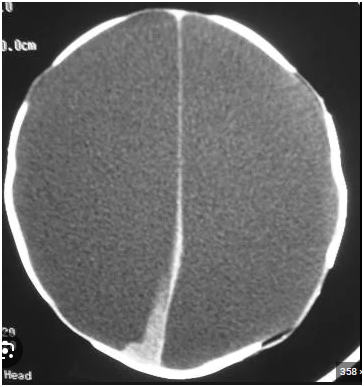

Hydranencephaly